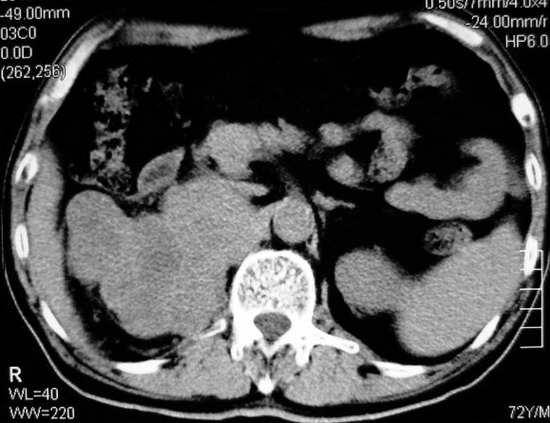

以下是引用杀毒软件在2008-11-17 19:15:00的发言:[br]考虑------右肾癌合并肾静脉---同侧肾上腺受侵可能性大

以下是引用zjzjr在2008-11-17 20:45:00的发言:[br]考虑------右肾癌合并肾静脉---同侧肾上腺受侵可能性大及腹膜后淋巴结转移.